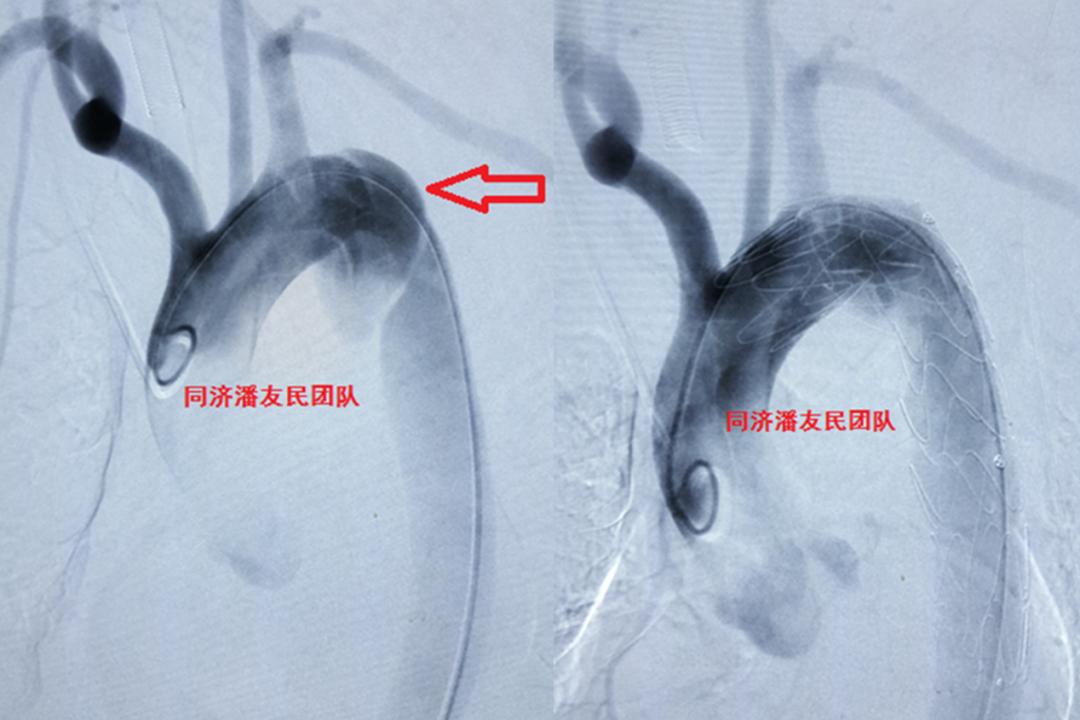

外伤性主动脉夹层进行腔内治疗,腹部外伤情况也进行了相应处理。患者出院前复查CTA,情况良好(图5)。